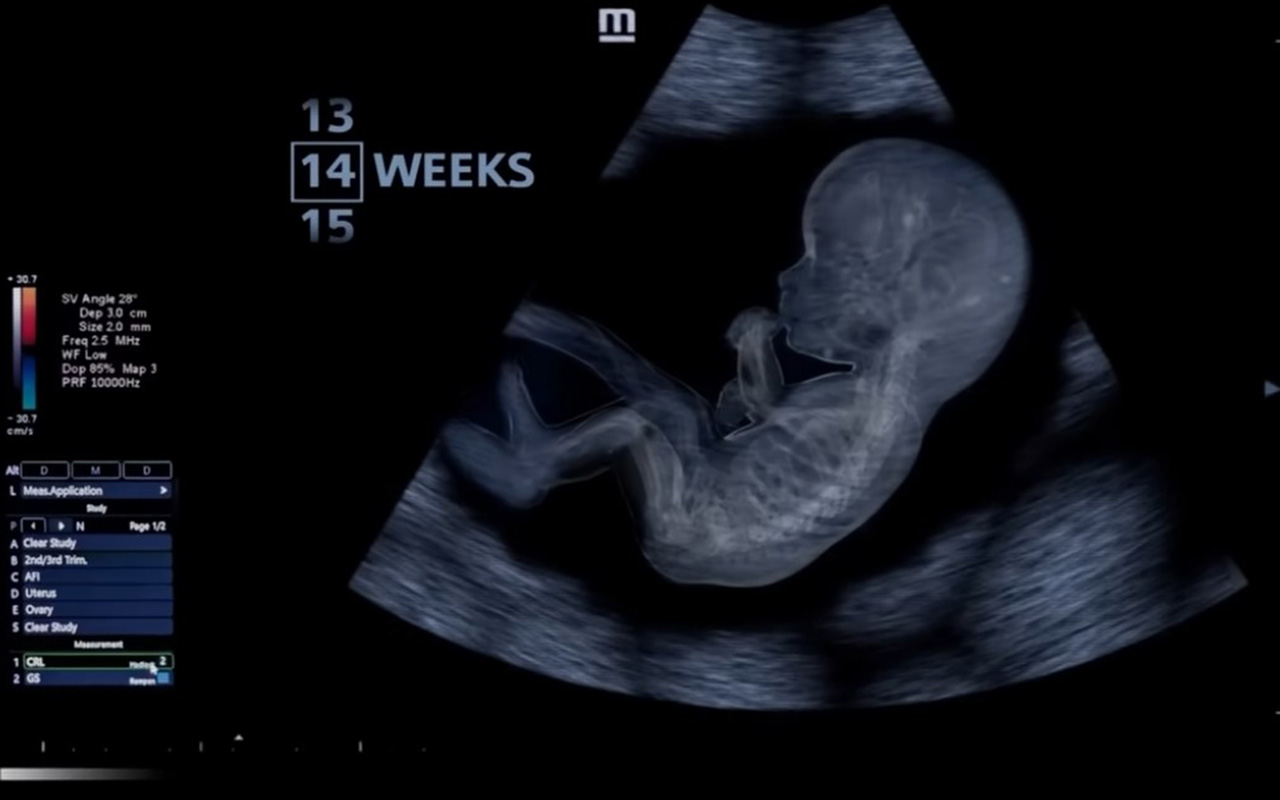

El video muestra las 14 semanas de gestación después de la fecundación. Aunque se trata de una etapa temprana del embarazo, los brazos y las piernas han comenzado a desarrollarse.

También revela que el sistema nervioso del bebé se está desarrollando rápidamente, formando nuevas conexiones entre el cerebro y el cuerpo. El corazón se fortalece cada vez más. Ahora late un poco más despacio que al principio del embarazo, a unas 150 pulsaciones por minuto.